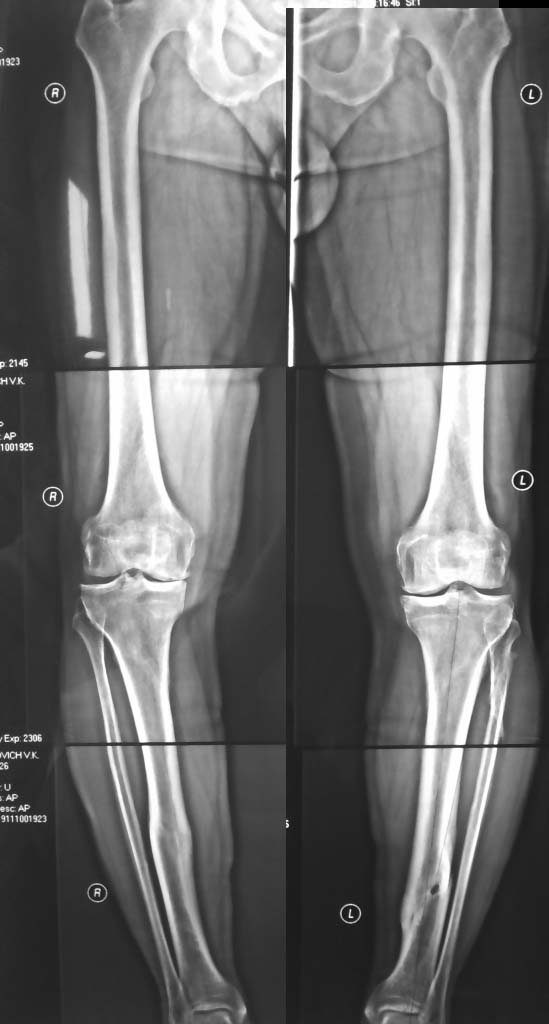

Одно из условий для одномыщелкового эндопротезирования – вальгус стресс тест должен полностью коррегировать варус, но не вызывать гиперкоррекцию . Так что сделайте рентгенограммы с вальгус стрессом, если получите полную коррекцию - я бы предпочел однополюсное эндопротезирование (конечно, если остальные условия соблюдены – интактная передняя крестовидная, полное разгибание и пассивное сгибание до 110 градусов). Слишком уж долга ждать конечных результатов после остеотомии, особенно если речь идет о двустороннем процессе.

Уважаемый Тарас Рокита,

Обе большеберцовые кости имеют 2 вершины деформации, т.е. речь идет о двухуровневых корригирующих остеотомиях. И только после этого ставить вопрос об одномыщелковом протезировании. При тотальном протезировании, возможно, можно будет обойтись только диафизарными остеомиями

(дистальная CORA). К сожалению, точнее сказать не могу - для расчетов Рг низкого качества.

я бы сделал НТО (+ клин), ось голени вполне приличная, "плюс клин" сильно не затруднит возможное тотальное протезирование.Образовавшийся дефект можно не замещать - закроется сам, а если использовать Puddu plate или ее аналаог -можно разрешать раннюю полную нагрузку.

Вариант, предложенный Александром Николаевичем, наиболее рациональный. Но я бы добавил небольшой сдвиг дистальных фрагментов большеберцовых костей кнаружи для разгрузки внутренних мыщелков. Так однозначно можно получить хороший положительный эффект.

Согласен с предложенной вальгизирующей остеотомией, только мне кажется, уровень должен быть выше, и ось желательно проводить через точку Фуджисава!